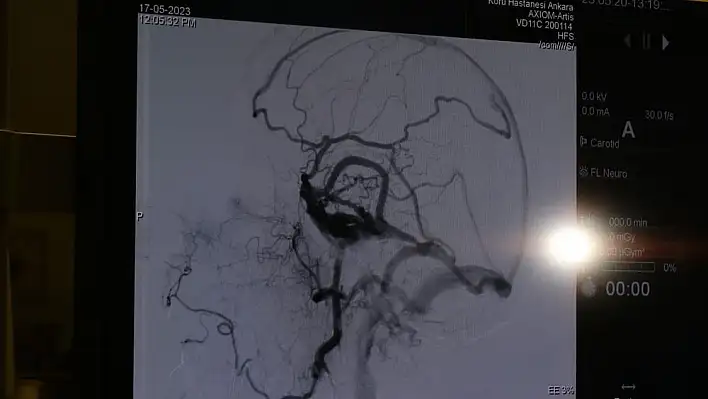

Özel Koru Ankara Hastanesi doktorlarından beyin ve sinir cerrahisi uzmanı Prof. Dr. Gülşah Bademci Adams Hakim Sendromu ya da daha yaygın olan adıyla erken bunamanın önüne geçmenin cerrahi müdahaleler ve düzenli kontrol ile mümkün olduğunu belirtti.

En çok uygulanan cerrahi yöntem, beyinde biriken sıvının karın boşluğuna aktarılmasıyla ilgili şant takılma ameliyatı olduğunu ifade eden Prof. Bademci”Ameliyattan sonra başarı oranlarımız yüzde 95 ile yüzde 99 arasındadır ..Özellikle hastalarımızın yürüme güçlükleri ve idrar kaçırma sorunları en erken düzelen bulgulardır. Hastalığın unutkanlık kısmı ise zaman içerisinde toparlanabilmektedir. Hastalık ile birlikte seyreden davranış bozukluğunun ise erken dönemde başarıyla düzeldiğini görmekteyiz. Hastanın kendisi bu sendroma sahip olduğunu kolaylıkla anlayamayabilir. Ama özellikle ailesi ve çevresi 40’lı 50’lili yaşlarda ki bireyin daha önceden olmayan özellikle öne doğru yıkılarak yürüme, idrar kaçırma veya mental yetilerde gerileme farkediyorsa ve çok ciddi bir unutkanlık ani olarak ortaya çıktıysa mutlaka beyin cerrahi bölümüne başvurmaları gerekmektedir” ifadelerini kullandı.